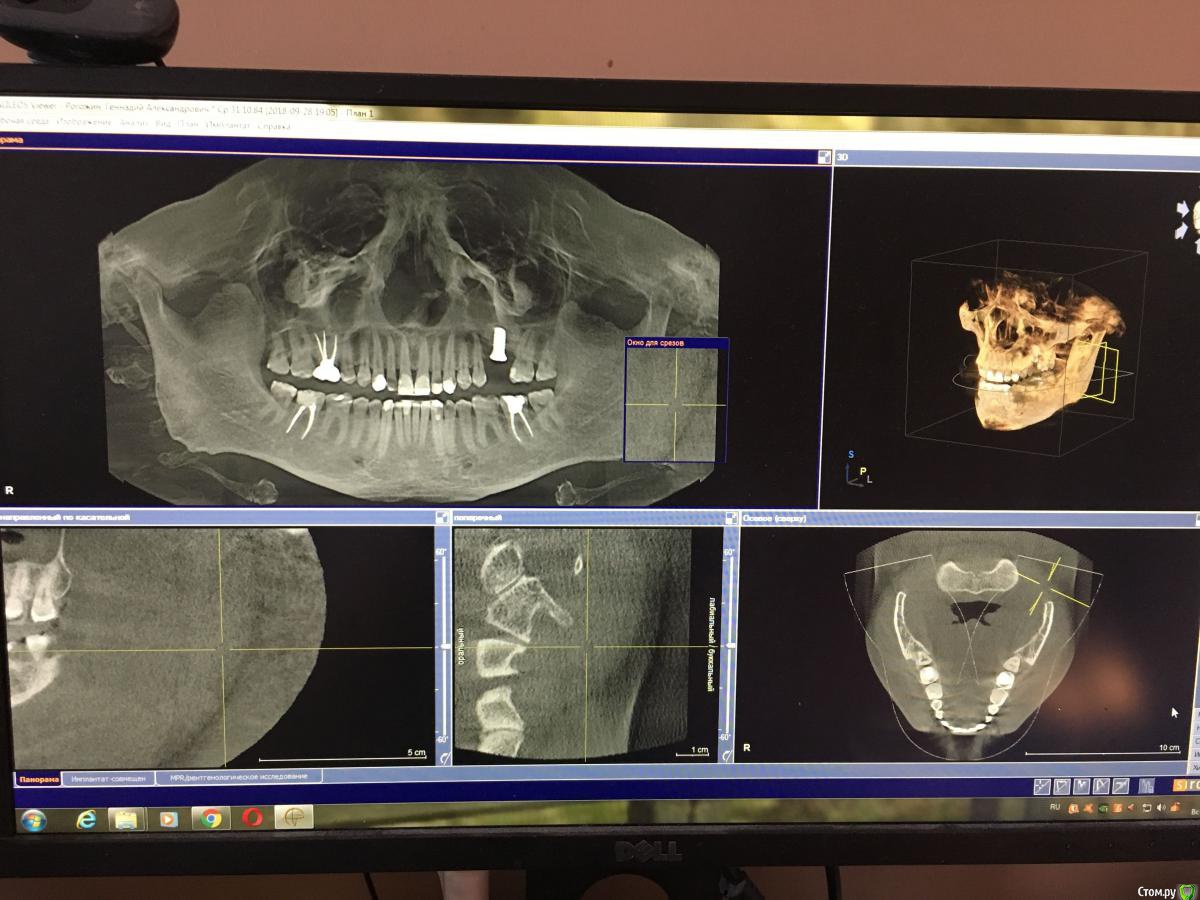

Геннадий1984 Опубликовано 5 мая, 2019 Автор Поделиться Опубликовано 5 мая, 2019 Прикрепляю фотографии Ссылка на комментарий

Геннадий1984 Опубликовано 5 мая, 2019 Поделиться Опубликовано 5 мая, 2019 Здравствуйте, прошу помочь советом. Зубами я начал заниматься в 27 лет, была сильная стираемость из-за не правильного прикуса. Сделал полную санацию, поставил металлические брекеты и три с половиной года их носил. Так как до установки брекетов зубы порядком стерлись, то после снятия нужно было поднимать прикус и восстановить эстетику на сколько это было возможно. Мой ортодонт не рекомендовала коронки, да и исходя из финансового положения решил поднимать прикус и восстанавливать зубы пломбировочным материалом. Часов за пять врач-скульптор "сваял" мне новые зубы и всё бы хорошо если бы пломбировочный материал держался больше года, но к сожалению опять всё обветшало. Особенно на нижней челюсти в переднем ряду слетают пломбы на фасаде. Замечу сразу, что чувствительности на холодное\горячее нет, даже у нижних пеньков, бруксизмом не страдаю. В сентябре прошлого года поставил имплант и в скором времени нужно будет ставить коронковую часть. Не могу понять как мне поступить, главная задача это эстетика, в остальном меня зубы устраивают. С 2012 года плотно общаюсь с ирригатором, электрической зубной щеткой и ополаскивателями как итог полностью прошла кровоточивость десен и забыл что такое кариес, но вот внешний вид(((. Вопросы: 1. Сначала поставить коронку на имплант, а затем поднимать прикус или наоборот?2. Существуют ли комбинированный вариант поднятия прикуса. То есть где-то коронки, а где-то поднять пломбировочным материалом?3. Если поднимают прикус, то это затрагивает все зубы без исключения? Следующим сообщением пришлю фотографии. Спасибо Ссылка на комментарий

Геннадий1984 Опубликовано 9 июня, 2019 Автор Поделиться Опубликовано 9 июня, 2019 Прошу подсказать, был на приеме и ортопед предлагает поднимать прикус на три мм за счет нижних зубов, поставив коронки, и так как со стороны языка верхние зубы от клыка до клыка сточены и обнажена эмаль на верхние также предлагает поставить коронки. К сожалению забыл уточнить у доктора, если прикус поднимаем за счет нижних зубов, могу ли я поставить коронку на имплант или нет до начала работ с зубами нижнего ряда? Врач далеко и связаться не потратив 5 часов на дорогу нет возможности. Спасибо. Ссылка на комментарий